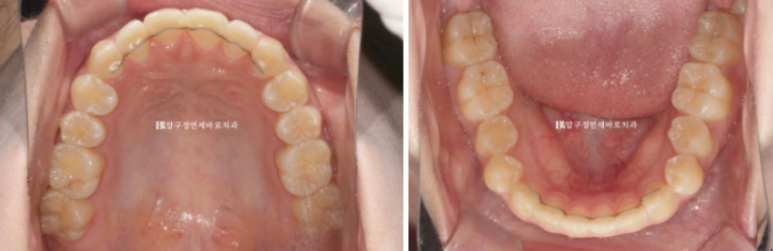

오늘은 덧니교정 앞니부분교정 소개해드리겠습니다.

6개월에 걸친 간단한 앞니 부분교정입니다.

23.12~24.06

단기 앞니 부분교정이지만 절단교합때문에 MTA나 2D와 같은 간단한 장치 말고 클리피씨로 치료한 증례입니다.

23년 12월 수능 후 환자분이 교정치료를 위해 내원했습니다.

23.12

뻗침도 없고 돌출도 없습니다.

해결하고자 하는 부분은 틀어진 덧니 입니다.

어금니 교합은 나쁘지 않은 편이라 단기 앞니 부분교정을 권유드렸습니다.